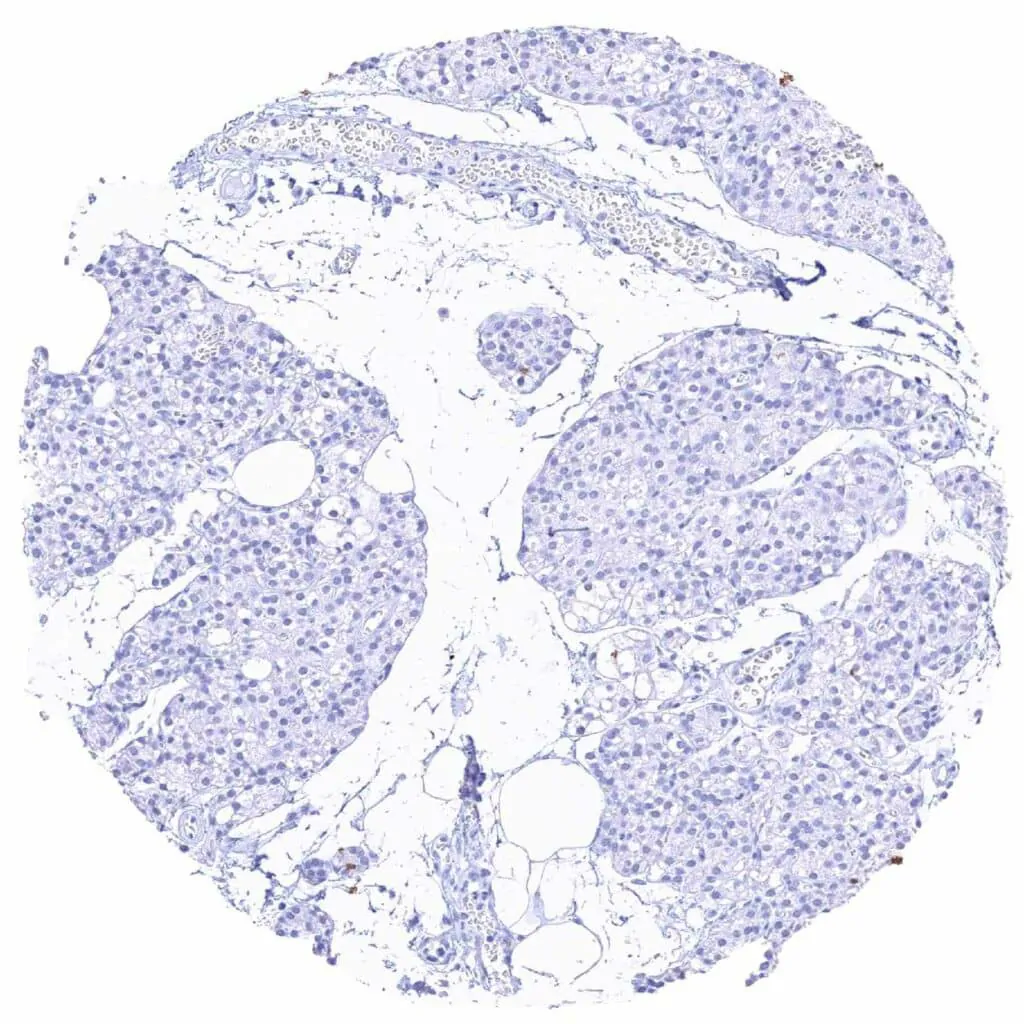

Testis